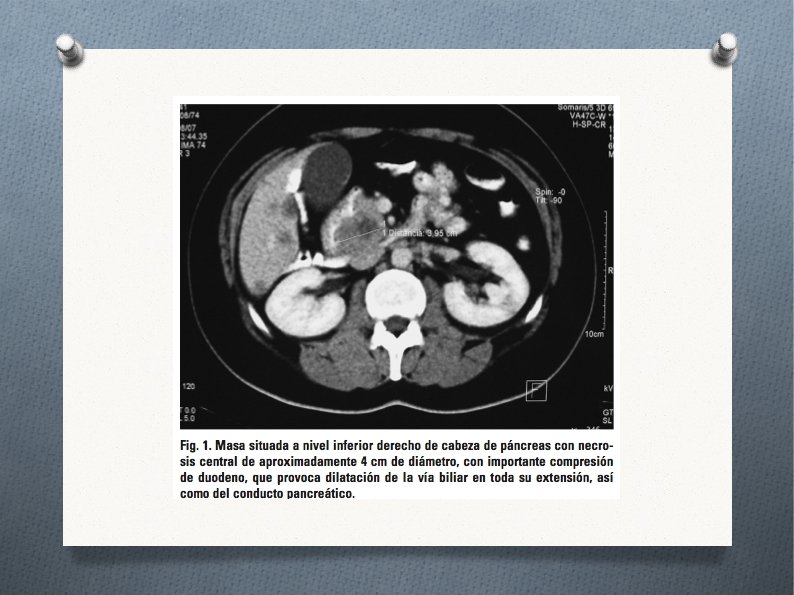

¿Qué PC solicitarías. . . ? ● ● TAC abdominal: múltiples imágenes en hígado, nodularesy bilobares, la mayor de unos 3 cm en segmento IV, compatibles con metástasis; masa situada a nivel inferior derecho de cabeza de páncreas, con necrosis central de aproximadamente 4 cm de diámetro, con importante compresión de duodeno, que provoca dilatación de la vía biliar en toda su extensión, así como del conducto pancreático; microadenopatías periféricas con vena y arteria mesentérica libres (figs. 1 y 2). Colangio-RM: masa en cabeza de páncreas; metástasis hepáticas.